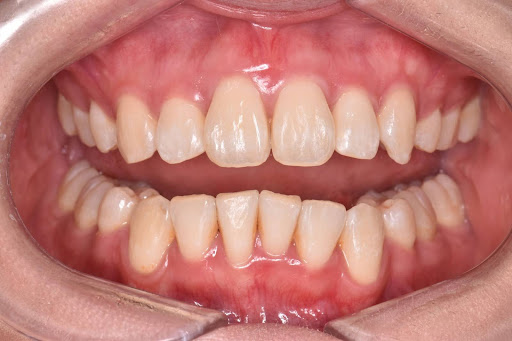

これがその術後の症例写真です。

フルプランのためかなり全体的に綺麗になりました。